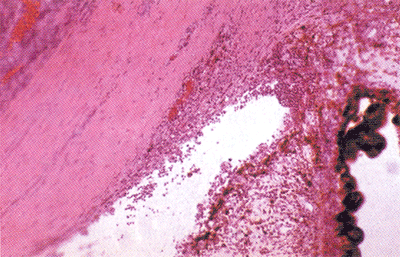

急性虹膜炎基础图谱

镜下见虹膜基质内有密集的多形核白细胞,是为急性炎症表现。前房内及小梁网内也积满多核白细胞,谓前房积脓。Schlemm管及深层集液管内充血。